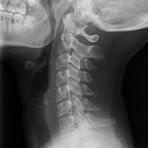

Röntgenaufnahme Halswirbelsäule

Die zu untersuchenden Anteile des Körpers werden meistens

in 2 unterschiedlichen Projektionsebenen dargestellt.

In einigen Körperregionen sind spezielle Zielaufnahmen notwendig.